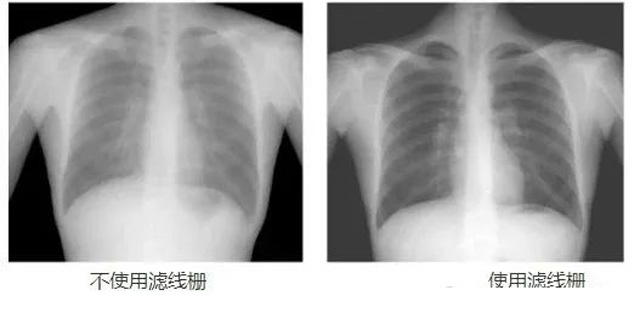

DR影像X射线在医学检查成像有着广泛的使用。但是它的散射线影响成像质量问题。滤线栅的发明使用很好的解决了这个问题,构造简单铅条粗,密度和栅比规格单一,能减散射线但吸收较多原发射线。伴随这医疗影像设备技术的发展,这个滤线栅的工艺制造技术有改进,铅条变薄,栅密度和栅比有更多的选择。特别是材料方面有新组合,填充物也依不同成像要求优化。特别是移动DR这类型的DR设备的出现,滤线栅也设计成立方便拆卸形的,方便使用。被照体情况决定是否使用,更好平衡成像质量与射线剂量。